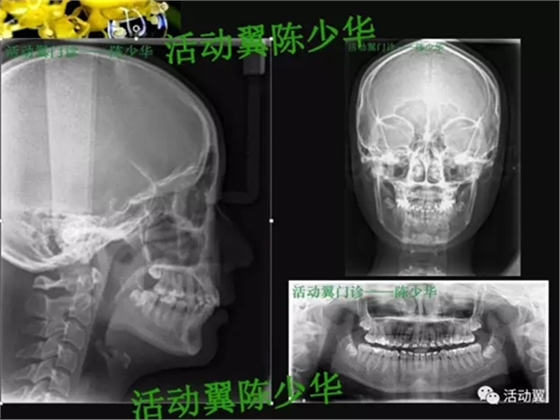

首頁正畸矯正 活動翼舌側(cè)病例——安氏2類1分類

活動翼舌側(cè)病例——安氏2類1分類

初診一般情況

•主訴:上牙前突,上下牙不齊,要求矯正。•牙列檢查:年輕恒牙17-27、37-47。磨牙尖牙遠中關(guān)系;前牙覆蓋6MM,深覆合2度,上牙前傾,下前牙輕度擁擠,Spee曲深。•面型:直面型。下頜輕度后縮。上下頜骨突度正常。顳下頜功能檢查未發(fā)現(xiàn)明顯異常。